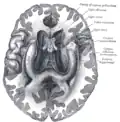

Base of brain (Tuber cinereum visible at center).

The tuber cinereum is the portion of hypothalamus forming the floor of the third ventricle situated between the optic chiasm, and the mammillary bodies.[1][2] The tuberal region is one of the three regions of the hypothalamus, the other two being the chiasmatic region and the mamillary region.[1]